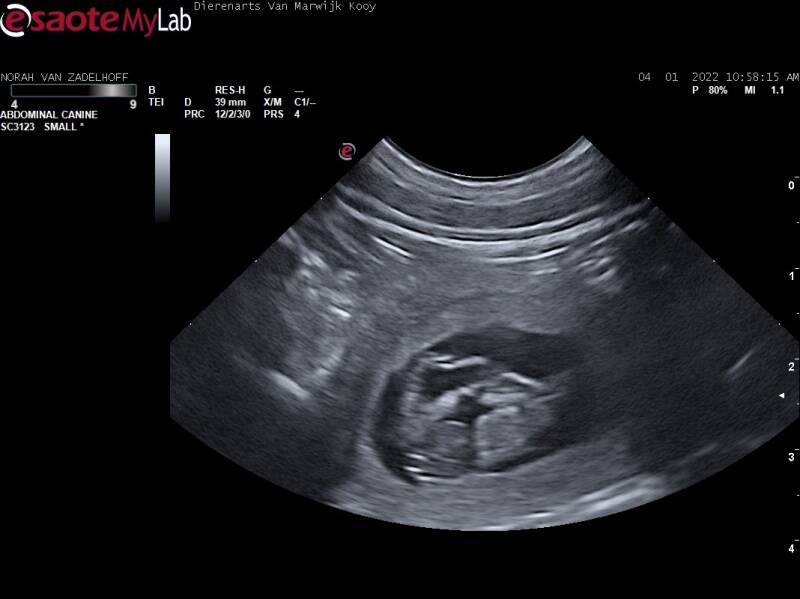

Drachtecho!

Vandaag (4 januari 2022) gingen we met Norah naar de dierenarts voor een drachtecho. We kregen te horen dat Norah drachtig was!! Hieronder kunt u enkele beelden van de drachtecho bekijken.